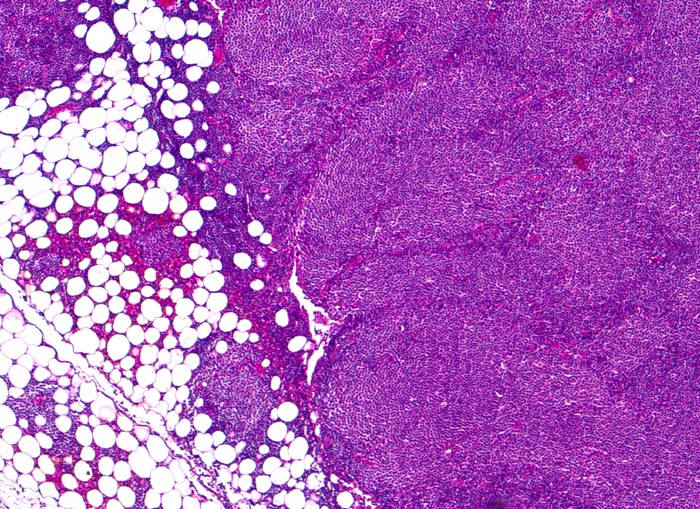

chronische lymphozytische Leukämie vom B-Zell Typ

Lymphknoten, inguinal

Diffuse CLL-Inifiltration des Lymphknotens mit Übergreifen des neoplastischen Infiltrates auf das umgebende Fettgewebe. Die hellen Areale entsprechen Proliferationszentren (Pseudofollikel) bestehend aus Lymphozyten, Prolymphozyten und Paraimmunoblasten.

Asymptomatische Patientin mit generalisierter Lymphknotenvergrösserung. Zufallsbefund.

50